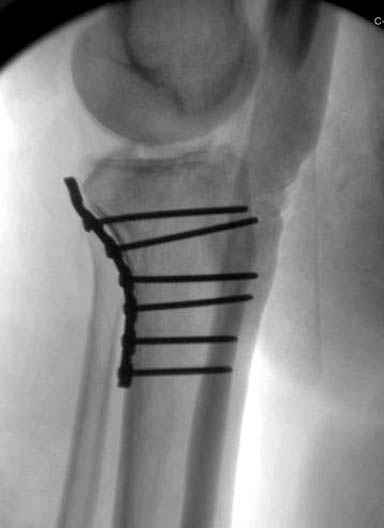

Уважаемые коллеги! В прошлую пятницу больной прооперирован - как и планировалось мыщелковая LCP от ChM. Малоинвазивно не получилось - один большой доступ :(. (но с минимальным скелетированием б/б кости). Наружный мыщелок собрали, но по контролю видно, что задне-медиальный отдел метаэпифиза смещен. Фиксировать не стали (?). 4-е сутки после операции - по м/тканям без проблем. Дополнительная иммобилизация синтетическим тутором.

P. S. перелом диафиза на контроле не совсем захвачен, но проблем там нет. Приношу извинения за низкое качество Р-грамм - выполнены на сканере (фотоаппарат не работает :)) .

Трудно поверить, что разрекламированная Ортопедическая школа Восточной Украины позволяет такие странные снимки? На прямом снимке сохранен общий контур плато, но не известна судьба импрессии суставной поверхности. На полубоковой?, оставлен без репозиции задне-медиальный отдел, и навряд ли после такой фиксации можно удовлетвориться результатом.

Такая ситуация характерна для многих, когда принимается ошибочное решение, т.е пытаются фиксировать одним имплантом переломы двух мыщелков. Латеральная пластина приемлема только для тех случаев, когда сохраняется интактным медиальный диафизарный кортекс и отсутствует фрагментация на верхушке медиального перелома.

Представленные снимки не информативны, нужны отдельные качественные снимки коленного сустава и голени без ротации.